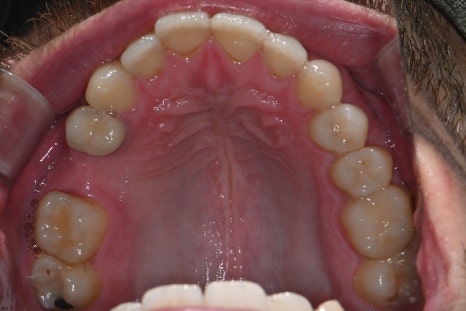

These are intraoral photos of the upper and lower teeth taken at the time of the visit.

Due to the loss of the second small molar on the upper right, implant treatment was needed.